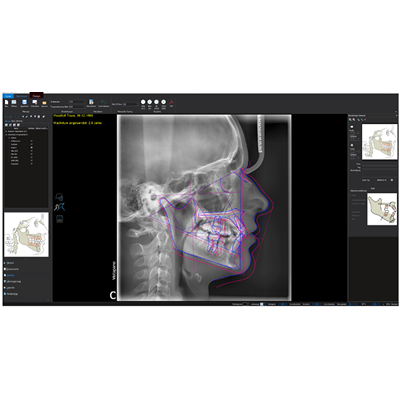

Cephalometric analyses

With the aid of innovative and extensive tools using artificial intelligence, cephalometric analyses can be completed within a few seconds using VistaSoft Trace. This user-friendly software add-on identifies reference points and soft tissue silhouettes automatically and plots them on the X-ray image.